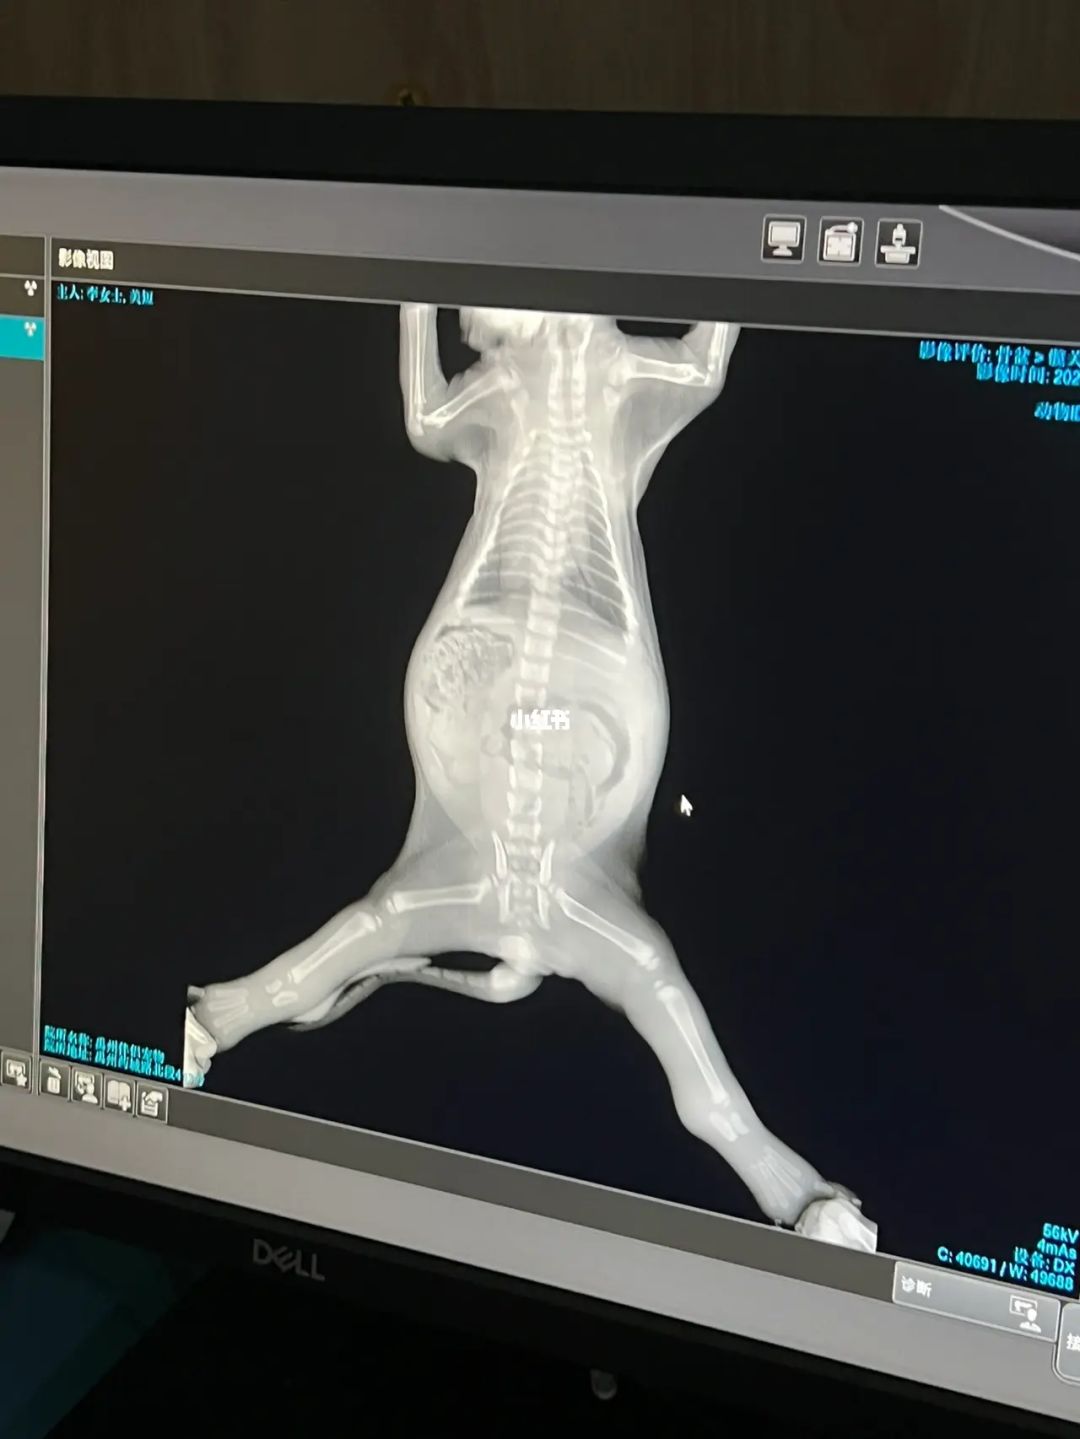

幼年时期,猫咪缺钙会直接影响身体发育,尤其是骨骼发育。到了老年时期,猫咪各方面的机能都在不断退化,钙的流失也比较快,只有补充足够的钙元素,才能避免骨骼退化。

幼猫缺钙可能会导致生长发育缓慢,主要表现是个子比较矮小,牙齿长得不齐等。

成猫缺钙会出现胃功能减弱,食欲不振,也会变得不愿意活动,不愿意行走或者跳跃,严重的可能还会影响猫咪走路。如果你发现猫咪日渐消瘦或者狂吃不胖,要留意是否缺钙。

老年猫缺钙容易骨质疏松,四肢无力,同时吸收能力减弱,抵抗力下降等。